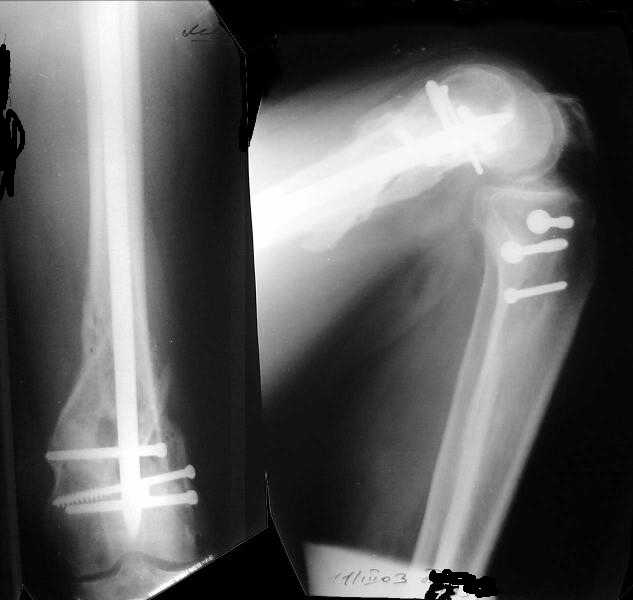

Мужчина 52 лет оперирован у нас 1,5 года назад по поводу перелома проксимального отдела большеберцовой кости. Все было неплохо, сгибал колено градусов до 60, ходил с полной нагрузкой, давно уже работал (служащий). Пару дней назад упал на скользкой улице - снимок в приложении. Какие предложения по лечению (пока первая мысль опять про закрытый интрамедуллярный остеосинтез)? И более широкий вопрос - как быть с локальным остеопорозом от бездействия после травм?

Merry Xmas!!! A male 52 years old was treated 1,5 years ago in our unit - ORIF of the proximal tibia. In 1 year follow-up all was OK - flexion 130, full WB, returned to work (white collar). Two days ago he fell on a slippery sidewalk - x-rays attached. How would you manage the injury? My first thought is closed nailing. And more common question - what we should do routinely with posttraumatic local osteoporosis? When full WB and function of the extremity is restored how long does a problem of such fractures exist?

Отправитель: Alexander Chelnokov 27 Декабрь 2003, 21:34

Sorry but I've just prepared postop images - attached. A solid 13 mm nail was used. A few degrees of recurvation appears to be which i missed on image intensifier. I'm still uncertain about

advantages/disadvantages of ante/retrograde nailing for such fractures.